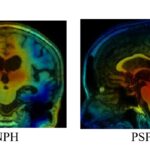

兵庫県立大学先端医療工学研究所と兵庫県立はりま姫路総合医療センターの共同研究グループは、治療可能な疾患である正常圧水頭 […]